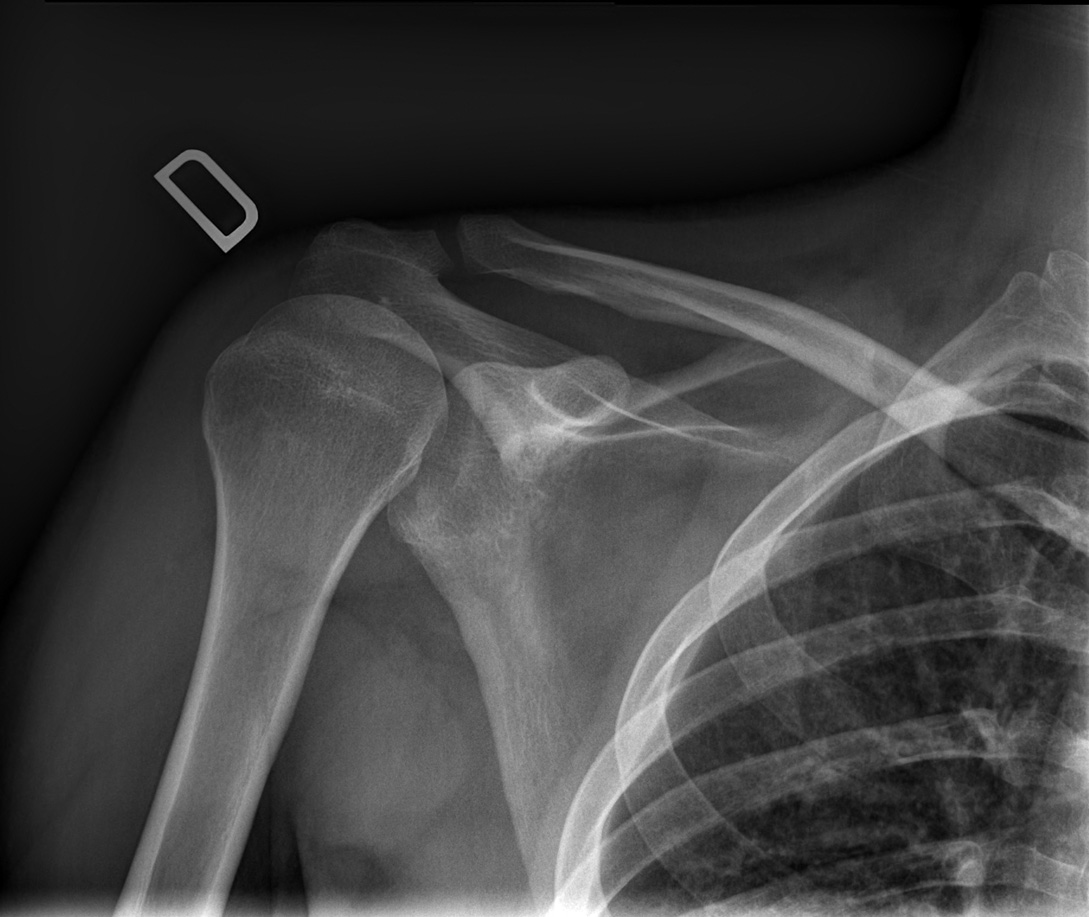

27-year-old male:

Left shoulder pain following a direct fall on the shoulder.

Acromioclavicular luxation

Bone misalignment

The left clavicule is displaced superiorly with increased acromioclavicular and coracoclavicular distance relative to the right side.

Displacement measurement

Superior displacement of the left clavicle with a coracoclavicular distance of 32 mm compared to 13 mm on the right side (146% displacement). This is thus a grade 5 acromioclavicular joint dislocation.